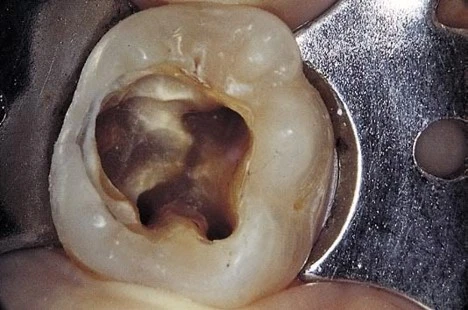

NHỮNG SAI SÓT TRONG MỞ TỦY thủng sàn tủy

Khắc phục:

1. Tuyệt đối không dùng động tác ấn mũi khoan xuống khi đã vào được buồng tủy (nên vuốt ngược lên để lấy sạch trần và sừng tủy).

2. Nắm vững kiến thức trước khi làm việc(GPH, thao tác mở tủy, các dụng cụ mở tủy đúng).

3. Hoãn lại việc mở tủy khi tìm không tìm được lối vào (hẹn lại lần khác) hoặc chụp phim kiểm tra rồi mới làm tiếp.

hoãn việc mở tủy

hình ảnh bị mũi khoan trụ ấn vào

Hình ảnh sàn tủy bị mũi khoan trụ lấn vào